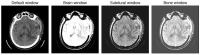

Intracranial hemorrhage (ICH) can lead to death or disability, which requires immediate action from radiologists. Due to the heavy workload, less experienced staff, and the complexity of subtle hemorrhages, a more intelligent and automated system is necessary to detect ICH. In literature, many artificial-intelligence-based methods are proposed. However, they are less accurate for ICH detection and subtype classification. Therefore, in this paper, we present a new methodology to improve the detection and subtype classification of ICH based on two parallel paths and a boosting technique. The first path employs the architecture of ResNet101-V2 to extract potential features from windowed slices, whereas Inception-V4 captures significant spatial information in the second path. Afterwards, the detection and subtype classification of ICH is performed by the light gradient boosting machine (LGBM) using the outputs of ResNet101-V2 and Inception-V4. Thus, the combined solution, known as ResNet101-V2, Inception-V4, and LGBM (Res-Inc-LGBM), is trained and tested over the brain computed tomography (CT) scans of CQ500 and Radiological Society of North America (RSNA) datasets. The experimental results state that the proposed solution efficiently obtains 97.7% accuracy, 96.5% sensitivity, and 97.4% F1 score using the RSNA dataset. Moreover, the proposed Res-Inc-LGBM outperforms the standard benchmarks for the detection and subtype classification of ICH regarding the accuracy, sensitivity, and F1 score. The results prove the significance of the proposed solution for its real-time application.